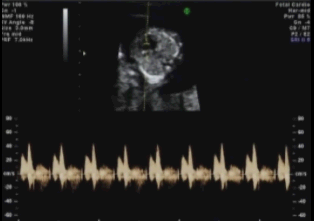

Diagnóstico ultrassonográfico:

- Cisto anecóico supra-tentorial em linha média, alongado com fluxo arteriovenoso ativo demonstrado pelo color Doppler.

- O defeito se desenvolve no início do primeiro trimestre, mas o aneurisma só se torna aparente à ultrassonografia no terceiro trimestre.

- Em 90% dos casos há insuficiência cardíaca de alto débito e hidropsia secundária.